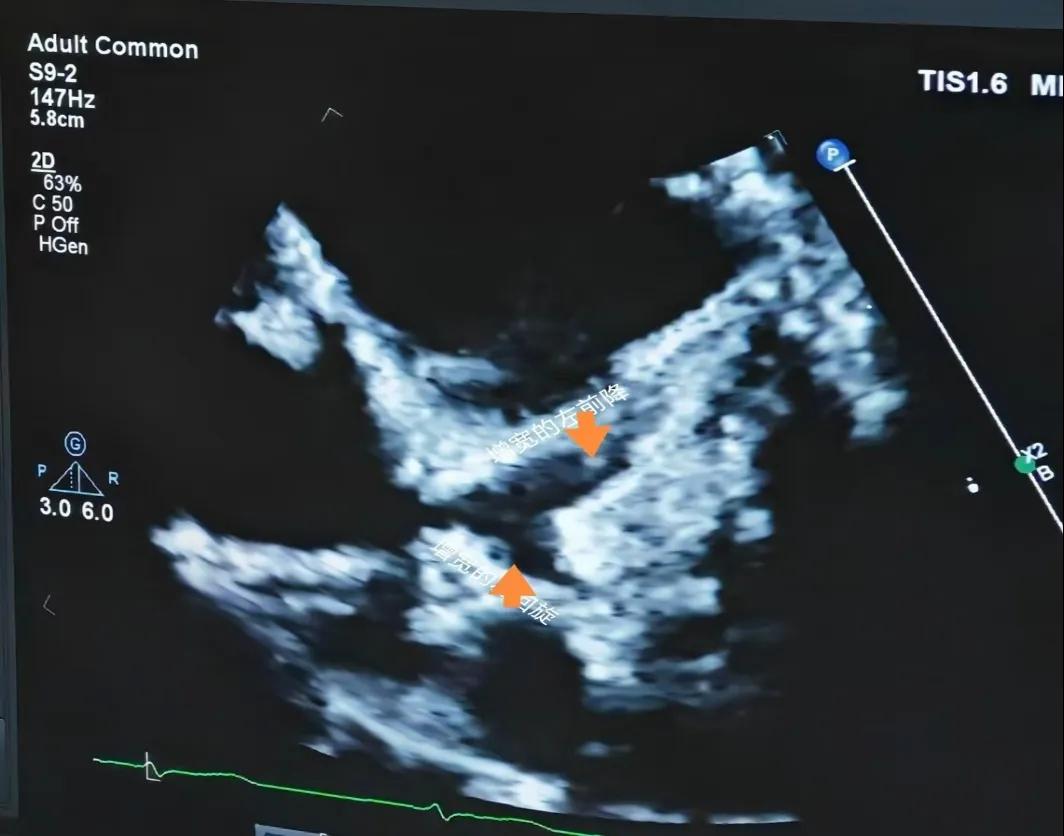

(川崎病患兒:增寬的左前降支和左回旋支)

(川崎病患兒:左冠狀動脈瘤)